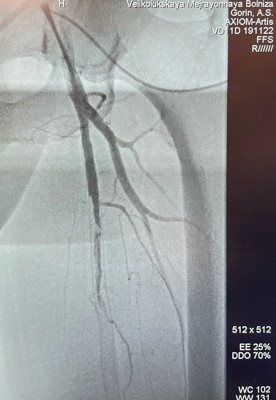

0Несколько лет назад в одной из клиник Санкт-Петербурга пациенту имплантировали стенты в бедренную артерию. После операции мужчина мог ходить без ограничений — результат был замечательным. Однако через год он снова стал испытывать боли в ногах при ходьбе. Обследование показало полную закупорку имплантированных стентов.

«В отделении РХМДиЛ провели реканализацию и ангиопластику в зоне окклюзии стентов. Кровоток восстановлен — теперь пациент снова может ходить без ограничений», — отметил Алексей Сергеевич.